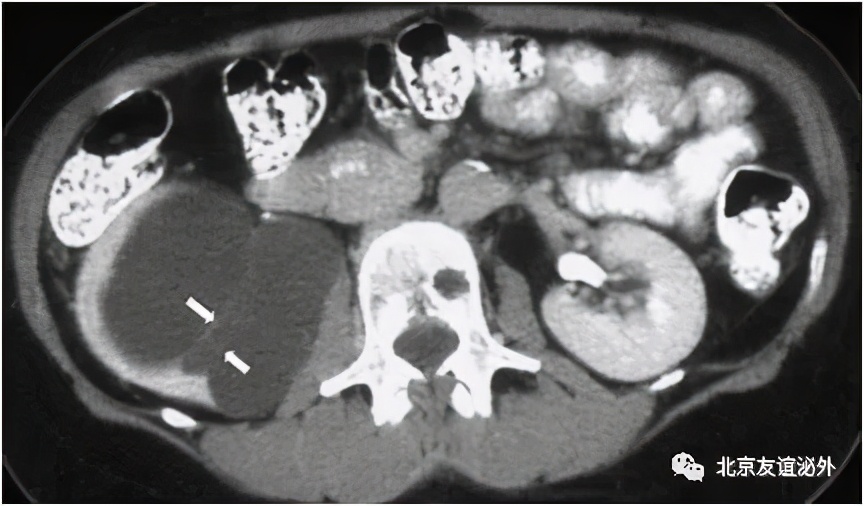

图6. Bosniak III级良性囊肿(肾脏淀粉样变)